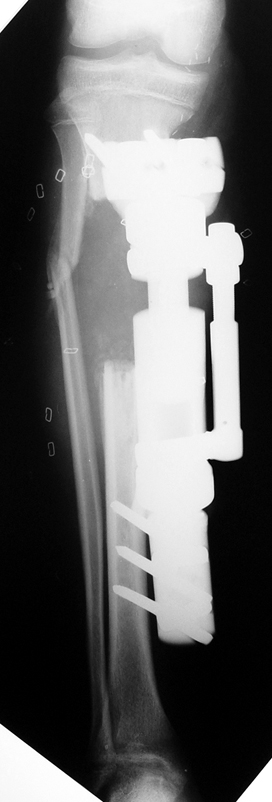

Debridement and resection of bone fragment from the pseudarhtosis area vascularized or nonvascularized fibula graft, vascularized muscle flaps, bone grafting followed internal fixation techniques make a option for treatment of pseudarthrosis treatment. But these treatment modalities may not correct deformity and leg-length discrepancy.

Case 2